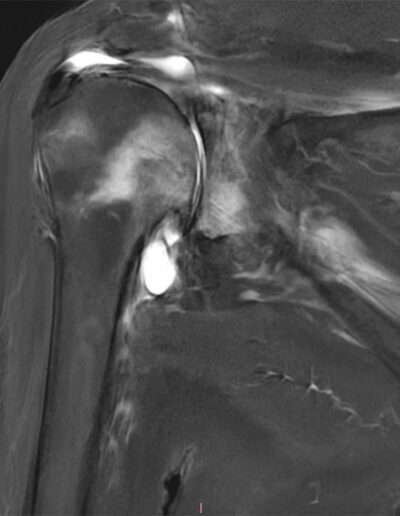

T06: TSA V-Shape

SHOULDER CASE SUMMARY:

Shoulder Left

Patient 81 y/o, Female, right-handed

• Painful loss of mobility for 3 years

• Infiltration and viscosupplementation without improvement